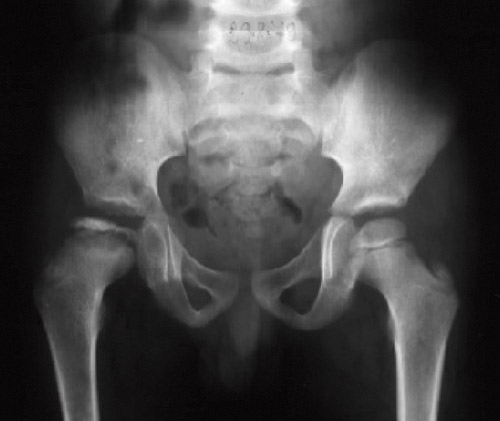

Røntgenbilder av hoftene i frontal- og sideprojeksjoner er fremdeles standard når det gjelder diagnostikk, med vurdering av nekrosens utbredelse, monitorering av forløp og evaluering av restdeformitet og leddkongruens.

Uavhengig av nekrosens utbredelse gjennomgår hofteleddet forskjellige røntgenologiske faser (12). Initialfasen er karakterisert ved forandringer i epifysens høyde, bredde og beinstruktur. I den påfølgende fragmenteringsfasen er epifysen helt eller delvis resorbert, med et typisk fragmentert utseende (fig 1). Siden går hoften gjennom tilhelingsfasen (reossifiseringsfasen).